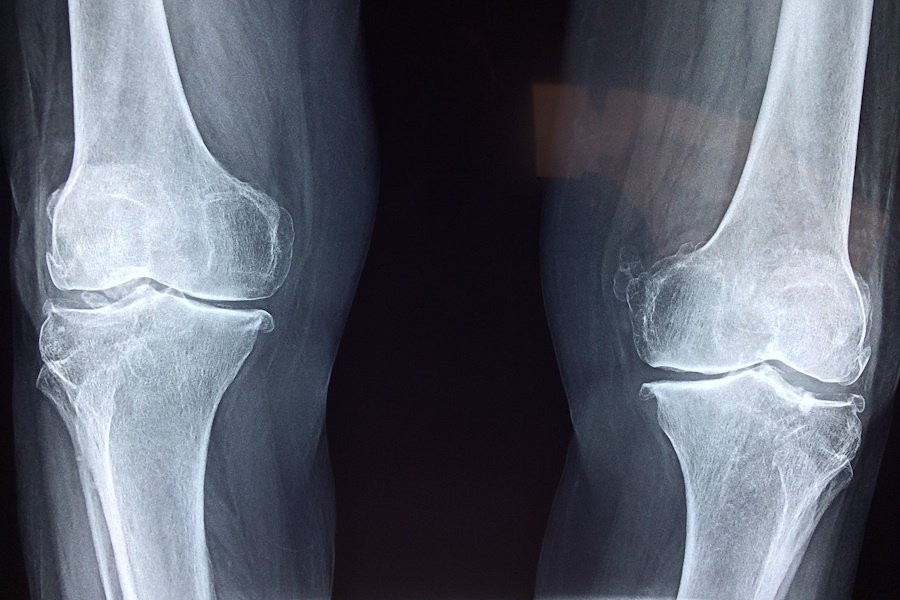

В новом исследовании, опубликованном на портале PNAS, ученые из Northwestern University и University of Wisconsin–Madison предложили инновационный подход к восстановлению гиалинового хряща — ключевого компонента суставов, который, к сожалению, не способен к самовосстановлению у взрослых.

В ходе экспериментов каркас был протестирован на овцах, суставы которых испытывают аналогичную нагрузку, как и у людей. Результаты показали, что новый материал способен выдерживать высокие механические нагрузки и способствует регенерации гиалинового хряща в поврежденных суставах. Это значительное достижение, так как многие предыдущие разработки не могли справиться с подобными задачами.